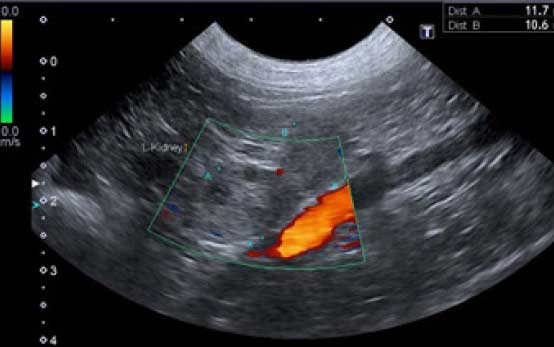

画像診断

X線検査や超音波検査により、内分泌疾患の原因や他の疾患がないか精査を行います。必要に応じて、MRIやCT検査によって下垂体や副腎の精査をすることもあります。